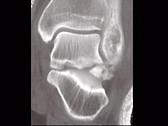

问题 男,28岁,从高处坠落后双足疼痛1月余,结合影像学检查,最可能的诊断是?(?)

选项 A.跟骨骨折 B.骰骨骨折 C.距骨骨折 D.舟状骨骨折 E.楔骨骨折

答案 C